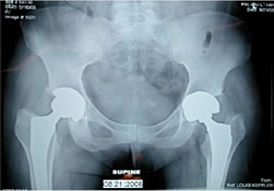

MoM bearing surfaces have encountered varied results over the years. The ability of offering larger diameter heads has increased the usage of MoM as one of the mechanisms to reduce hip dislocations. However, issues have been raised with regards to cup spinout, high trace elements, and metal sensitivity.

L. Keppler - cup spin out 7 weeks post-op |

MoM cup migration 2 years post-op |